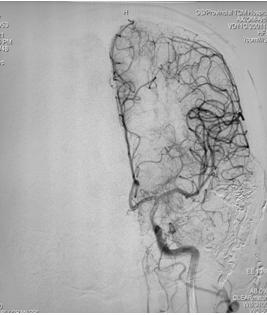

手术过程:术中采取弹簧圈辅助填塞,Onyx液态胶多支供血动脉分次栓塞治疗措施,由于供血动脉纵横交错,手术难道可想而知,经过4小时的艰难努力,于18:30手术结束,术程顺利,成功帮助患者填塞了动静脉瘘,为患者解决了病痛。